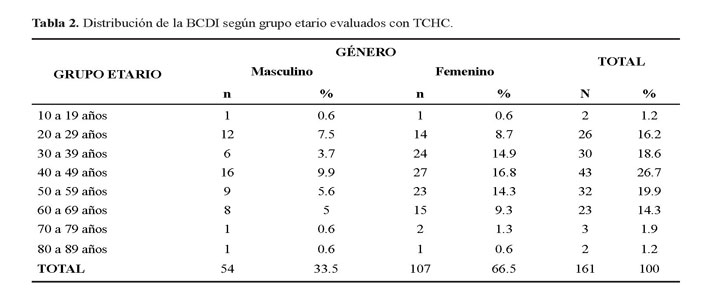

La edad de la población fue de un rango etario de 10 a 89 años, con una media de 44,8 ± 14 años. La BCDI se encontró en su mayoría en la quinta década de vida con un 26.7% (43 casos) y en su minoría en la segunda y novena década con un 1.2% (2 casos) (Tabla 2).